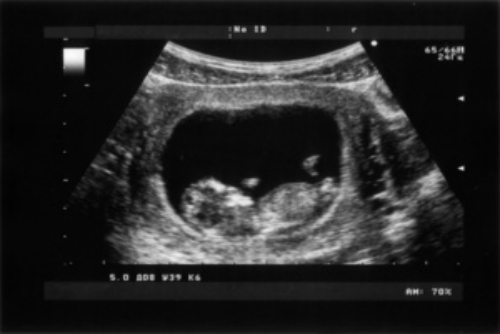

胎兒超聲檢查是指在超聲監測下,對胎兒進行的全面檢查,觀察胎兒各個器官發育情況,以判斷胎兒是否存在畸形,或者發現胎兒生長受限、胎兒宮內窘迫等情況。

1、檢查內容:對胎兒進行系統超聲檢查,可以明確胎兒各個器官系統發育情況,如測量頭圍、腹圍、大腿長度、股骨長度、肱骨長度,觀察胎兒是否存在畸形,或者發現胎兒生長受限、股骨短縮等情況。還可以觀察羊水、胎盤及臍帶情況,判斷是否存在前置胎盤、胎盤早剝等異常情況;

2、檢查方法:常規超聲檢查是將探頭放在孕婦腹部,進行掃查,要求檢查時被檢者的皮膚和器官穿透超聲探頭。而四維彩超是在三維彩超的基礎上,增加時間的維度參數進行的檢查,可以動態性地觀察胎兒的結構,還可以測量羊水的多少,觀察胎兒是否存在畸形,或者發現胎兒宮內窘迫等情況;

超聲檢測1

3、檢查時間:一般要求在妊娠22-28周進行,部分孕婦需要提前進行,因為孕周不確定,超聲判斷的孕周與實際孕周會有差距。而中晚期妊娠的超聲檢查需要根據胎兒各個器官的發育情況,以及孕婦的具體情況決定;

4、其他:如果檢查時胎兒的胎動過于頻繁或明顯減少,都可能會導致超聲檢查不準確。若胎兒的手部、腳部等部位遮擋住超聲探頭,也會影響檢查結果。

除上述檢查項目外,胎兒超聲檢查還包括臍帶測量、骨測量等其他方面的檢查。通過胎兒超聲檢查可以了解胎兒的具體發育情況,如果出現異常情況,醫生會及時給予處理。